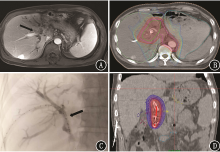

Yang Wenbo, Xiao Li, Bi Jianqiang, Sun Yunchuan. Application of192Ir brachytherapy combined with external beam radiation and biliary stent in the treatment of unresectable hilar cholangiocarcinoma[J]. Journal of International Oncology, 2022, 49(2): 95-99.